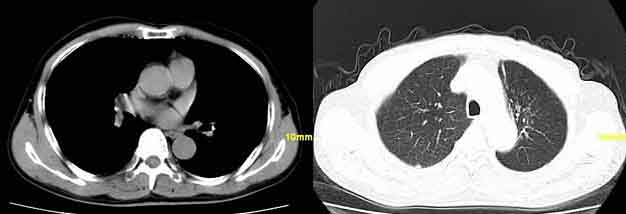

患者,男,76,反复咳血,余病史不详。

因为;纵隔窗内见钙化影,病灶呈条索样,并且病人反复咳血,所以考虑结核。

左肺上叶前段片絮状模糊影,考虑感染性病变,以炎性改变可能性大,建议抗炎后复查或进一步结合实验室检查,毕竟病人有咯血史,应引起重视。

咯血强烈提示肿瘤